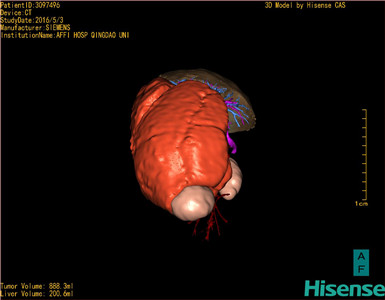

将0.625mm双源薄层CT资料的静脉期和动脉期Dicom格式文件导入海信CAS系统。

通过调节窗宽窗位调整CT序号,对肿瘤,肝实质,胆囊,下腔静脉,肿瘤,肝动脉、门静脉及肝静脉等进行三维重建;系统自动计算肿瘤体积和肝脏体积。(模拟手术操作,自动计算切除肿瘤体积。

术前三维重建:

重建图片